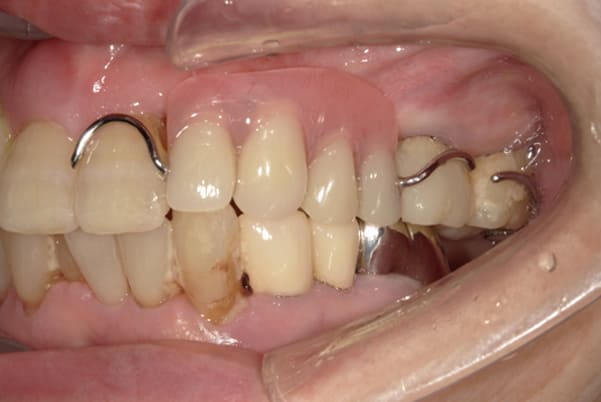

上あごに接する入れ歯に違和感がありになっていたとのことで、プラスチックが大きく削られた入れ歯をされていました。

そのため入れ歯の安定が悪く、お食事の際に入れ歯が動き、がたつきを感じられている状態でした。

前歯にバネにより見た目の問題も抱えておられました。

かみ合わせが低くなった歯を本来の高さに戻し、保険では使用できない歯に負担のかかりずらいバネで、歯の保存、審美性を確保しました。

前歯にバネを設定せず、見えない奥歯に維持力をもたせたバネを用い、またバネのかかる歯の負担軽減を目的に、被せ物は繋げることで強度を増す設計とすることで、入れ歯が動かずガタつき、審美性不良が解消されました。

部分入れ歯と対合歯

入れ歯を修理する中で、入れ歯の上あごの接触面積ではなく、厚みに対しての違和感と診断し、薄い金属を用いた従来の厚みを1/3程度にした入れ歯にすることにより違和感は消失しました。